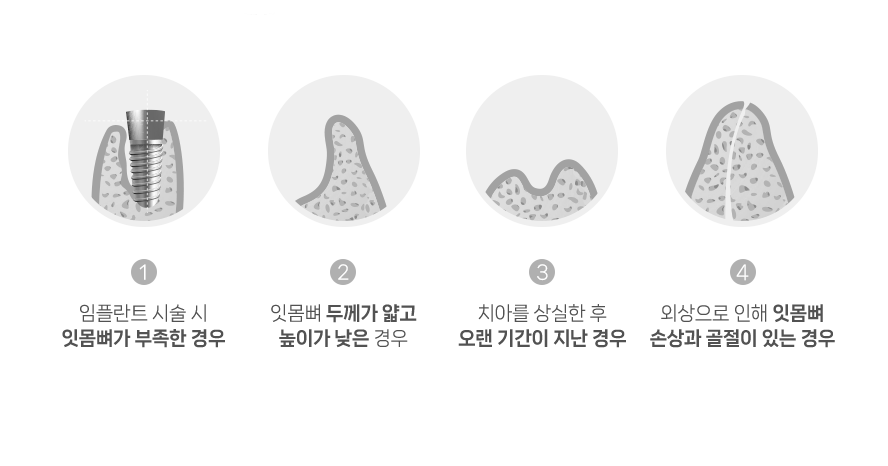

임플란트 주위를 둘러싼

뼈가 튼튼해야

임플란트가 튼튼하게 고정되어 오랫동안 안정적으로 사용할 수 있습니다.